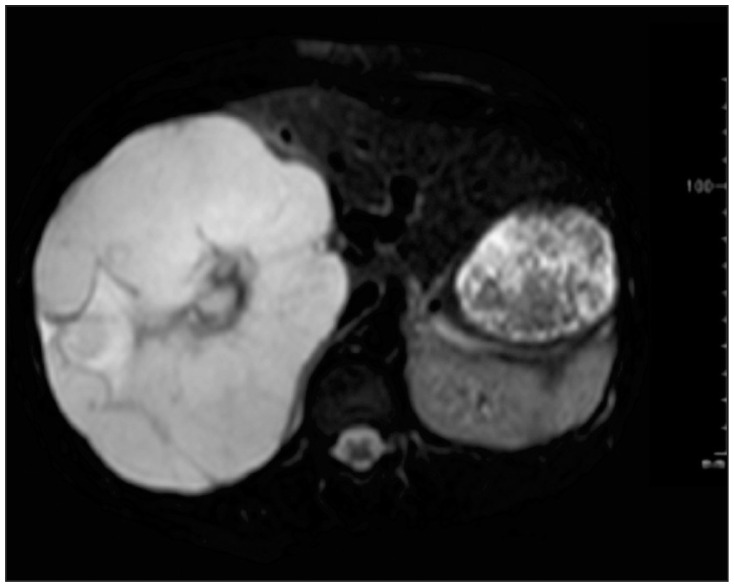

Figure 2.

Coronal section of MRI T2-weighted image at 12 GW revealed a giant hemangioma, 20 cm in diameter, in the enlarged right lobe of the liver. Right hepatic vein and anterior segmental branch of the portal vein were compressed by the tumor.